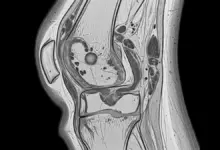

É uma das explicações mais lembradas. O cisto de Baker é um acúmulo de líquido sinovial na parte de trás do joelho, geralmente associado a algum problema dentro da articulação, como desgaste da cartilagem, inflamação ou lesão do menisco.

Pode aparecer como uma “bola” palpável, com sensação de pressão e piora ao estender totalmente o joelho.

Quando há suspeita de lesão interna (menisco, cartilagem, ligamentos) ou quando o quadro persiste, a ressonância magnética pode ser indicada.